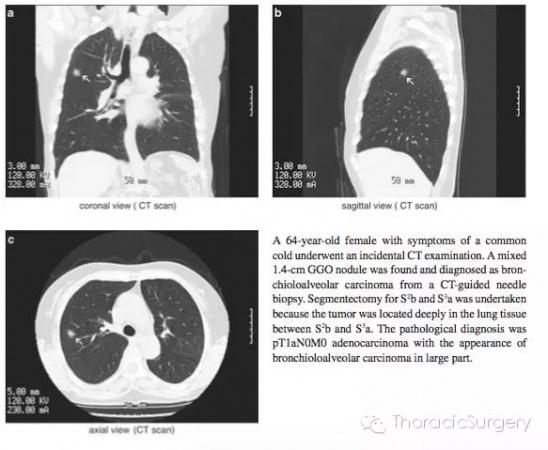

患者,女性,64岁,因反复出现感冒症状,CT检查发现右上肺1.4cm的GGO。CT引导下的穿刺活检病理证实为细支气管肺泡癌。由于肿瘤位于肺组织深部,予以S2b + S3a肺段切除。最终的病理学诊断为pT1aN0M0细支气管肺泡癌。

图.3.5.1 有时患者需要接受S2b+S3a肺段切除。例如,<2cm的细支气管肺泡癌位于肺组织深部,位于S3a和S2b交界处,可采用该手术方案,因为切除S2和S3两个肺段可能影响患者的肺功能。气管插管后通过支气管镜明确B1,B2和B3分支形状和尺寸。本书中的图片是段支气管和动脉最常见的分支类型,即右上支气管分为B1和B2和B3;A1和A3段间动脉分支源于肺动脉上干。A2a和A2b源于升支;段间静脉源于尖段和中央静脉是最常见的形式。第三肋间推荐作为S2段切除的主操作孔。